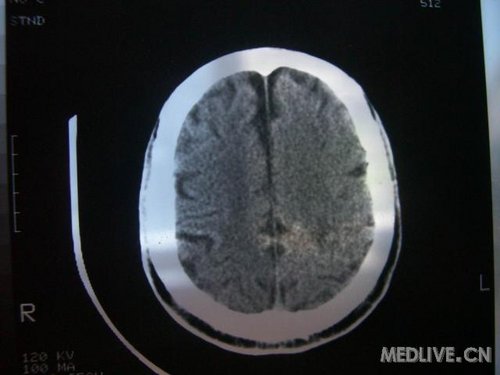

病人男性 73岁 市民 以“幻听、幻视两天,言语含糊、精神错乱一天”入院。

两天前无诱因出现幻听、幻视,描素眼前有彩色的圆圈,听见有人说话(但说什么不详),一天前出现胡言乱语,言语含糊,精神错乱,问话不答,行走略有不稳,来我院就诊,门诊头CT检查:(下面有片)入院后查体不合作,表情淡漠,问话不答,大致检查了一下,颅神经未见明显异常,颈软,右手活动似忽略差。其他检查不配合。脑电图:广泛轻-中度异常。

既往史:半年前曾患“右侧脑梗塞”但无明显后遗症,生活能自理,无高血压、糖尿病、心脏病史。

此次入院时的片子: